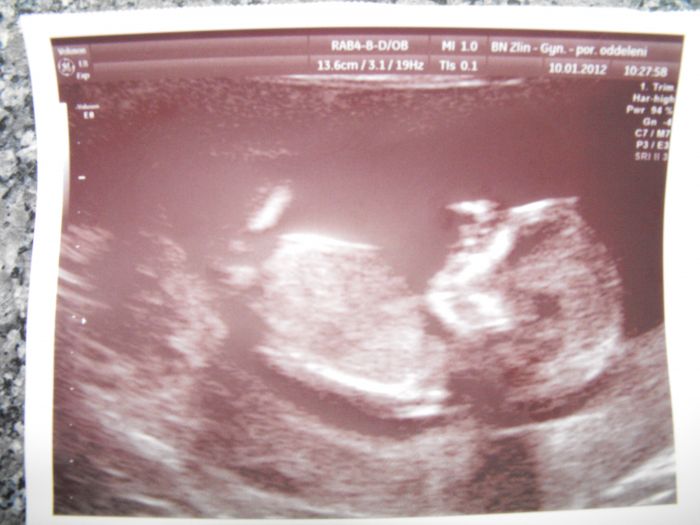

Ahoj tak já jsem včera taky dopadla dobře nebo spíše miminko.Je zdravé,takže super a možná to bude holčička říkala paní dr.

Jo a dnes jsem 13tt.,je o dva dny větší než podle ms a TP mám 18.7.

Alenko tak o placentě Dr. nic neříkal, ale prý je vše v pořádku :-). Jsem dnes podle UZ i podle poslední MS 12+1 a mám o 1 cm menší miminko než ty...:-), tak snad vás ten 13 tt. doženeme :-). To je hezký, vkračuješ už do 2. trimestru. Já si ještě týden počkám. Na další sono jsem objednaná na 7.2., tak doufám, že mi už taky doktor řekne, co čekáme :-)